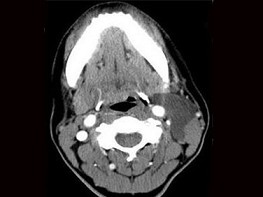

| 十产岁患者,女性,因颈前正中包块3年入院,查体:颈前胸锁乳突肌前缘上1/3外可触及一圆形包块,囊性,无压痛,不随吞咽上下活动。 |

6.CT检查结果见下图,本患者应考虑为 ( )![]() ![]() ![]() ![]() |

| 正确答案:6.C;7.E |